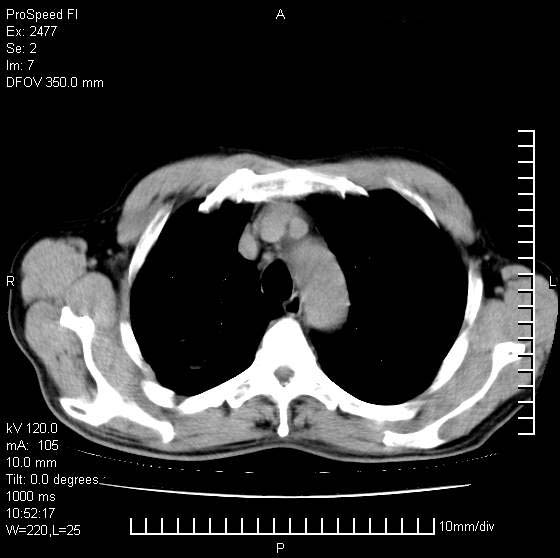

以下是引用天南地北在2007-10-9 14:29:00的发言:[br]1:右上肺结核[br]2:右肺下叶肿块:不支持肺癌,首先考虑炎性病变-肺脓疡可能性大[br]理由:1:临床病史支持,肺脓肿症状不明显应该是不规则服药造成。[br] 2:肿块边缘模糊,周围可见炎性渗出,长毛刺,内见支气管征,不过有点不规则。[br] 我感觉下肺癌这个诊断有点偏左,建议积极抗炎治疗后复查

以下是引用卜一在2007-10-9 15:55:00的发言:[br][br] [br] 1:右上肺结核[br]2:右肺下叶肿块:不支持肺癌,首先考虑炎性病变-肺脓疡可能性大[br]理由:1:临床病史支持,肺脓肿症状不明显应该是不规则服药造成。[br] 2:肿块边缘模糊,周围可见炎性渗出,长毛刺,内见空气支气管征,不过有点不规则。[br] 我感觉下肺癌这个诊断有点偏左,建议积极抗炎治疗后复查![br]支持! [br] [br] [br]

以下是引用hhcckk在2007-10-9 15:18:00的发言:[br]右上肺病灶考虑结核,病灶多种形态并存(纤维化、增殖性病灶并存)[br]右下肺病灶比较难说,个人意见更趋向于“天南地北”的诊断----肺脓肿[br]1、病人有明显的寒战,高热,肿瘤病人很少出现[br]2、病灶周围的肺纹理走向柔和,没有肿瘤病灶常见的集束征[br]3、病灶边缘的毛刺较长,恶性肿瘤多为短毛刺[br]痰中血丝和病人的年龄是两个不利于良性肿块的因素,建议早点活检

以下是引用ydx_74在2007-10-9 15:53:00的发言:[br]右上肺结核,右下中心性肺癌可能大,肺门淋巴结肿大。